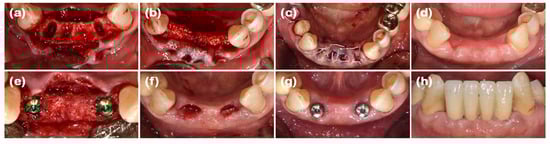

2.4. Case 4 (Multiple Posterior Implants, Peri-Implantitis, and Collapsed Ridge of Implant Removal Region)